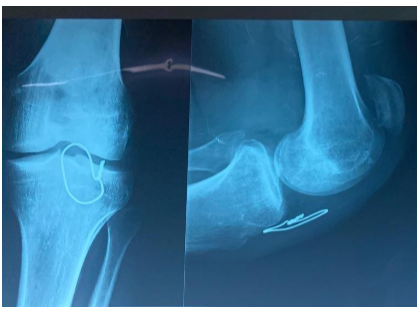

Mr. , a 43-year-old man, presented 1 year after a sports-related injury to the left knee. He had initially been treated surgically in another hospital, where a diagnosis of patellar tendon rupture had been made. He consulted us due to persistent symptoms. Examination revealed quadriceps atrophy, loss of active knee extension, and a high-riding patella palpable in the supracondylar region. Radiographs confirmed patella alta and the presence of a protective steel wire from previous surgery (Fig. 5).

Figure 5: Standard radiograph of the left knee showing patella alta with cerclage wire in place – Patient 3.